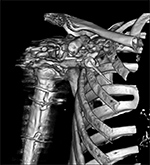

Figure 5A Figure 5B Figure 6A Figure 6B

3d reconstruction 3d reconstruction Dual energy CT Dual energy CT

Periprosthetic 3D Reconstruction. (A) 3D reconstruction of osseous anatomy surrounding right total shoulder arthroplasty without dual-energy technique demonstrates significant artifact limiting evaluation of hardware and glenohumeral joint. (B) Dual-energy CT 3D reconstruction focused on metallic hardware demonstrates excellent visualization of hardware with metaglene screw fracture (arrow). Dual Energy CT. (A) Axial CT image acquired with dual energy technique demonstrates minimal artifact secondary to sacroiliac joint screws. (B) Coronal multi-planar reformation demonstrates excellent visualization of the osseous anatomy and hardware with further minimization of artifact.